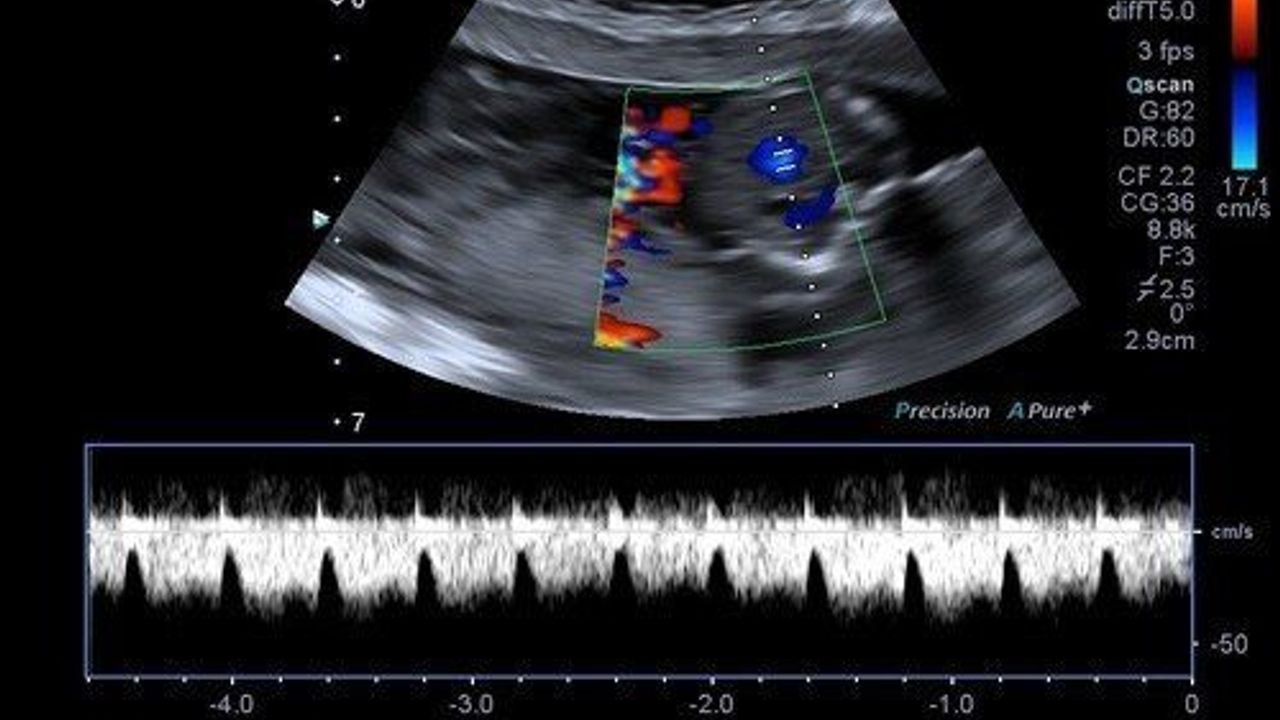

Mukaddes Polat'ın karın içerisini kaplayan kitle tespit edilmesi üzerine kendilerine başvurduğunu anlatan Akselim, "Yaptığımız muayene ve görüntülemeler sonrasında miyom olduğunu düşündüğümüz yaklaşık 30-35 cm’lik, karnın neredeyse tamamını kaplayan lezyon için karar verip hastamızı ameliyata aldık. Rahmin üst ve arka duvarını kaplayarak, miadında bir gebelikteki rahim boyutuna kadar büyümüş bir miyom olduğunu tespit ettik. Hastanın rahmini koruyarak myomektomi ameliyatını gerçekleştirdik. Patolojik olarak incelemeye gönderdiğimizde herhangi kötü huylu bir durumla karşılaşmadık. Kitle yaklaşık 2 bin 700 kg ağırlığındaydı. Hastamız kısa sürede sağlığına kavuştu. Bu tür durumlarda erken teşhis ve zamanında müdahale çok önemlidir." şeklinde konuştu.